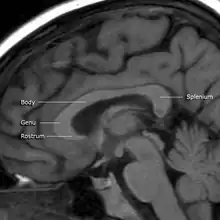

A number of separate nerve tracts, classed as subregions of the corpus callosum, connect different parts of the hemispheres. The main ones are known as the genu, the rostrum, the trunk or body, and the splenium.[4]

The corpus callosum has four main parts – individual nerve tracts that connect different parts of the hemispheres. These are the rostrum, the genu, the trunk or body, and the splenium.[4] A narrowed part between the trunk and the splenium is known as the isthmus. Fibres from the trunk and the splenium known together as the tapetum form the roof of each lateral ventricle.[6]

The front part of the corpus callosum, towards the frontal lobes, is called the genu ("knee"). The genu curves downward and backward in front of the septum pellucidum, diminishing greatly in thickness. The lower, much thinner part is the rostrum and is connected below with the lamina terminalis, which stretches from the interventricular foramina to the recess at the base of the optic stalk. The rostrum is named for its resemblance to a bird's beak.

The end part of the corpus callosum, towards the cerebellum, is called the splenium. This is the thickest part, and overlaps the tela choroidea of the third ventricle and the midbrain, and ends in a thick, convex, free border. Splenium translates as "bandage" in Greek.

The trunk of the corpus callosum lies between the splenium and the genu.